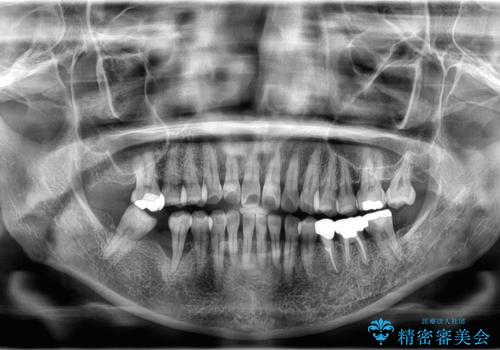

- 歯がぐらぐらしてきて怖いとのことで、当院に来院された患者様です。

右下小臼歯は歯周病で大きな骨欠損を認めていました。

できる限り歯が保存できるように治療したいとのことでエムドゲインを用いた再生治療を行っています。

欠損歯に関しては、奥歯をアップライトさせてインプラント埋入予定です。